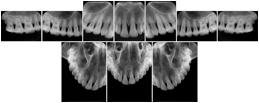

2. A patient requests cosmetic surgery to enhance their facial appearance. The case requires consultation between an orthodontist in New York and an oral surgeon in California. The cephalometric series of 2D projections constructed from a volumetric CT data set that is used for the discussion is arranged by a Structured Display for transfer between the two practitioners.

Cephalometric Series Structured Display

Figure OO-2. Cephalometric Series Structured Display